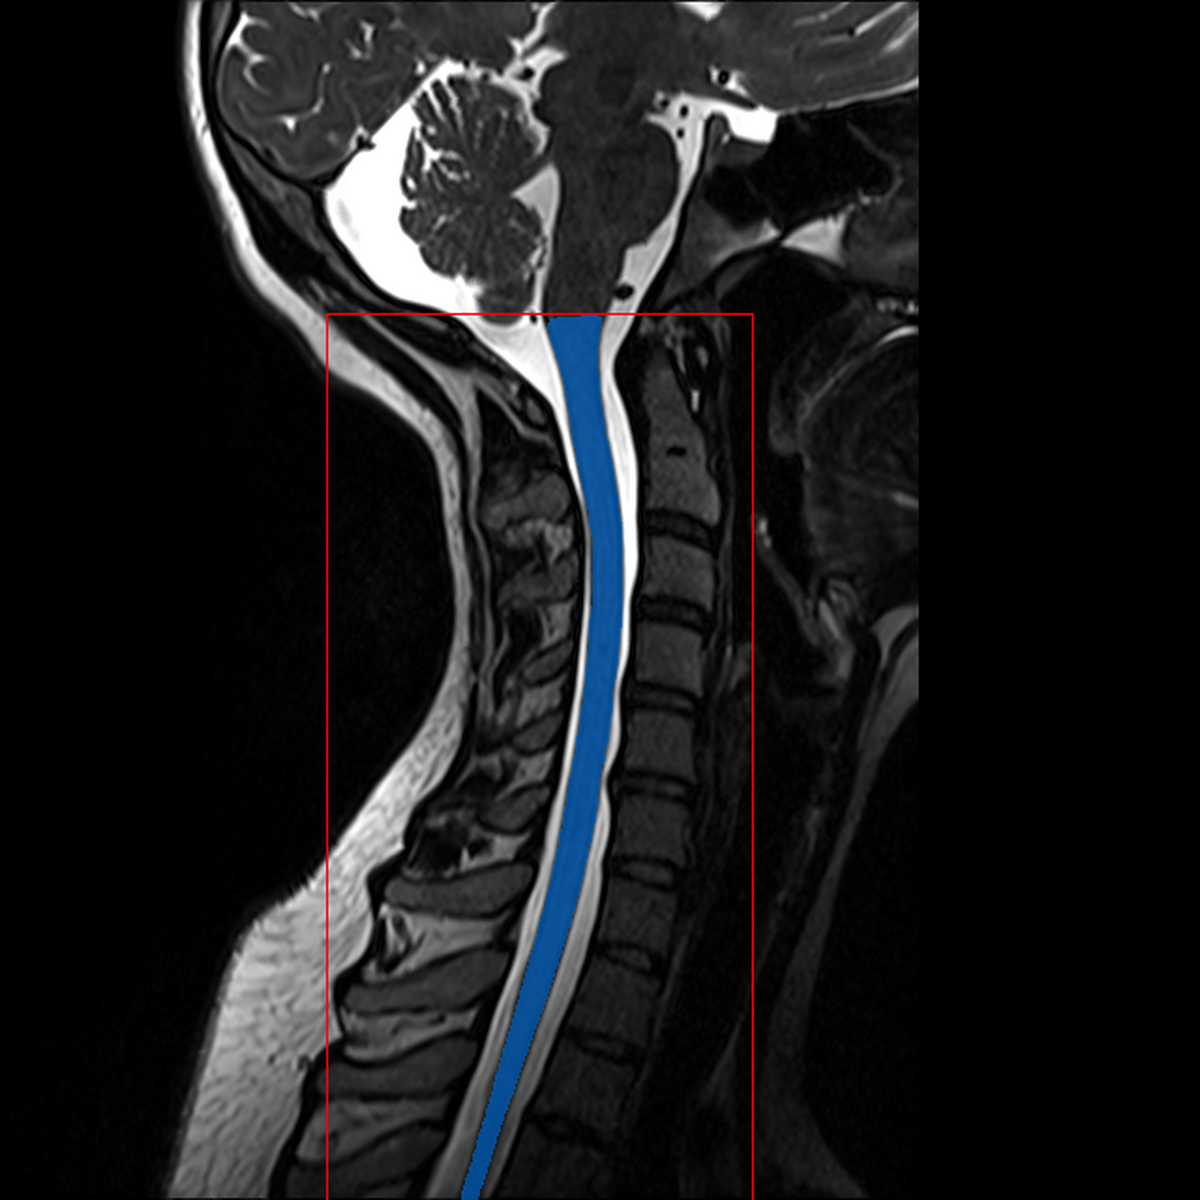

QC: Crop Box Sagittal

What to look for:

- ✅ Blue contour (cord mask) follows the spinal cord

- ✅ Red contour (crop box) encompasses the full cord region

- ❌ FAIL: Crop box extends into brain or misses cord